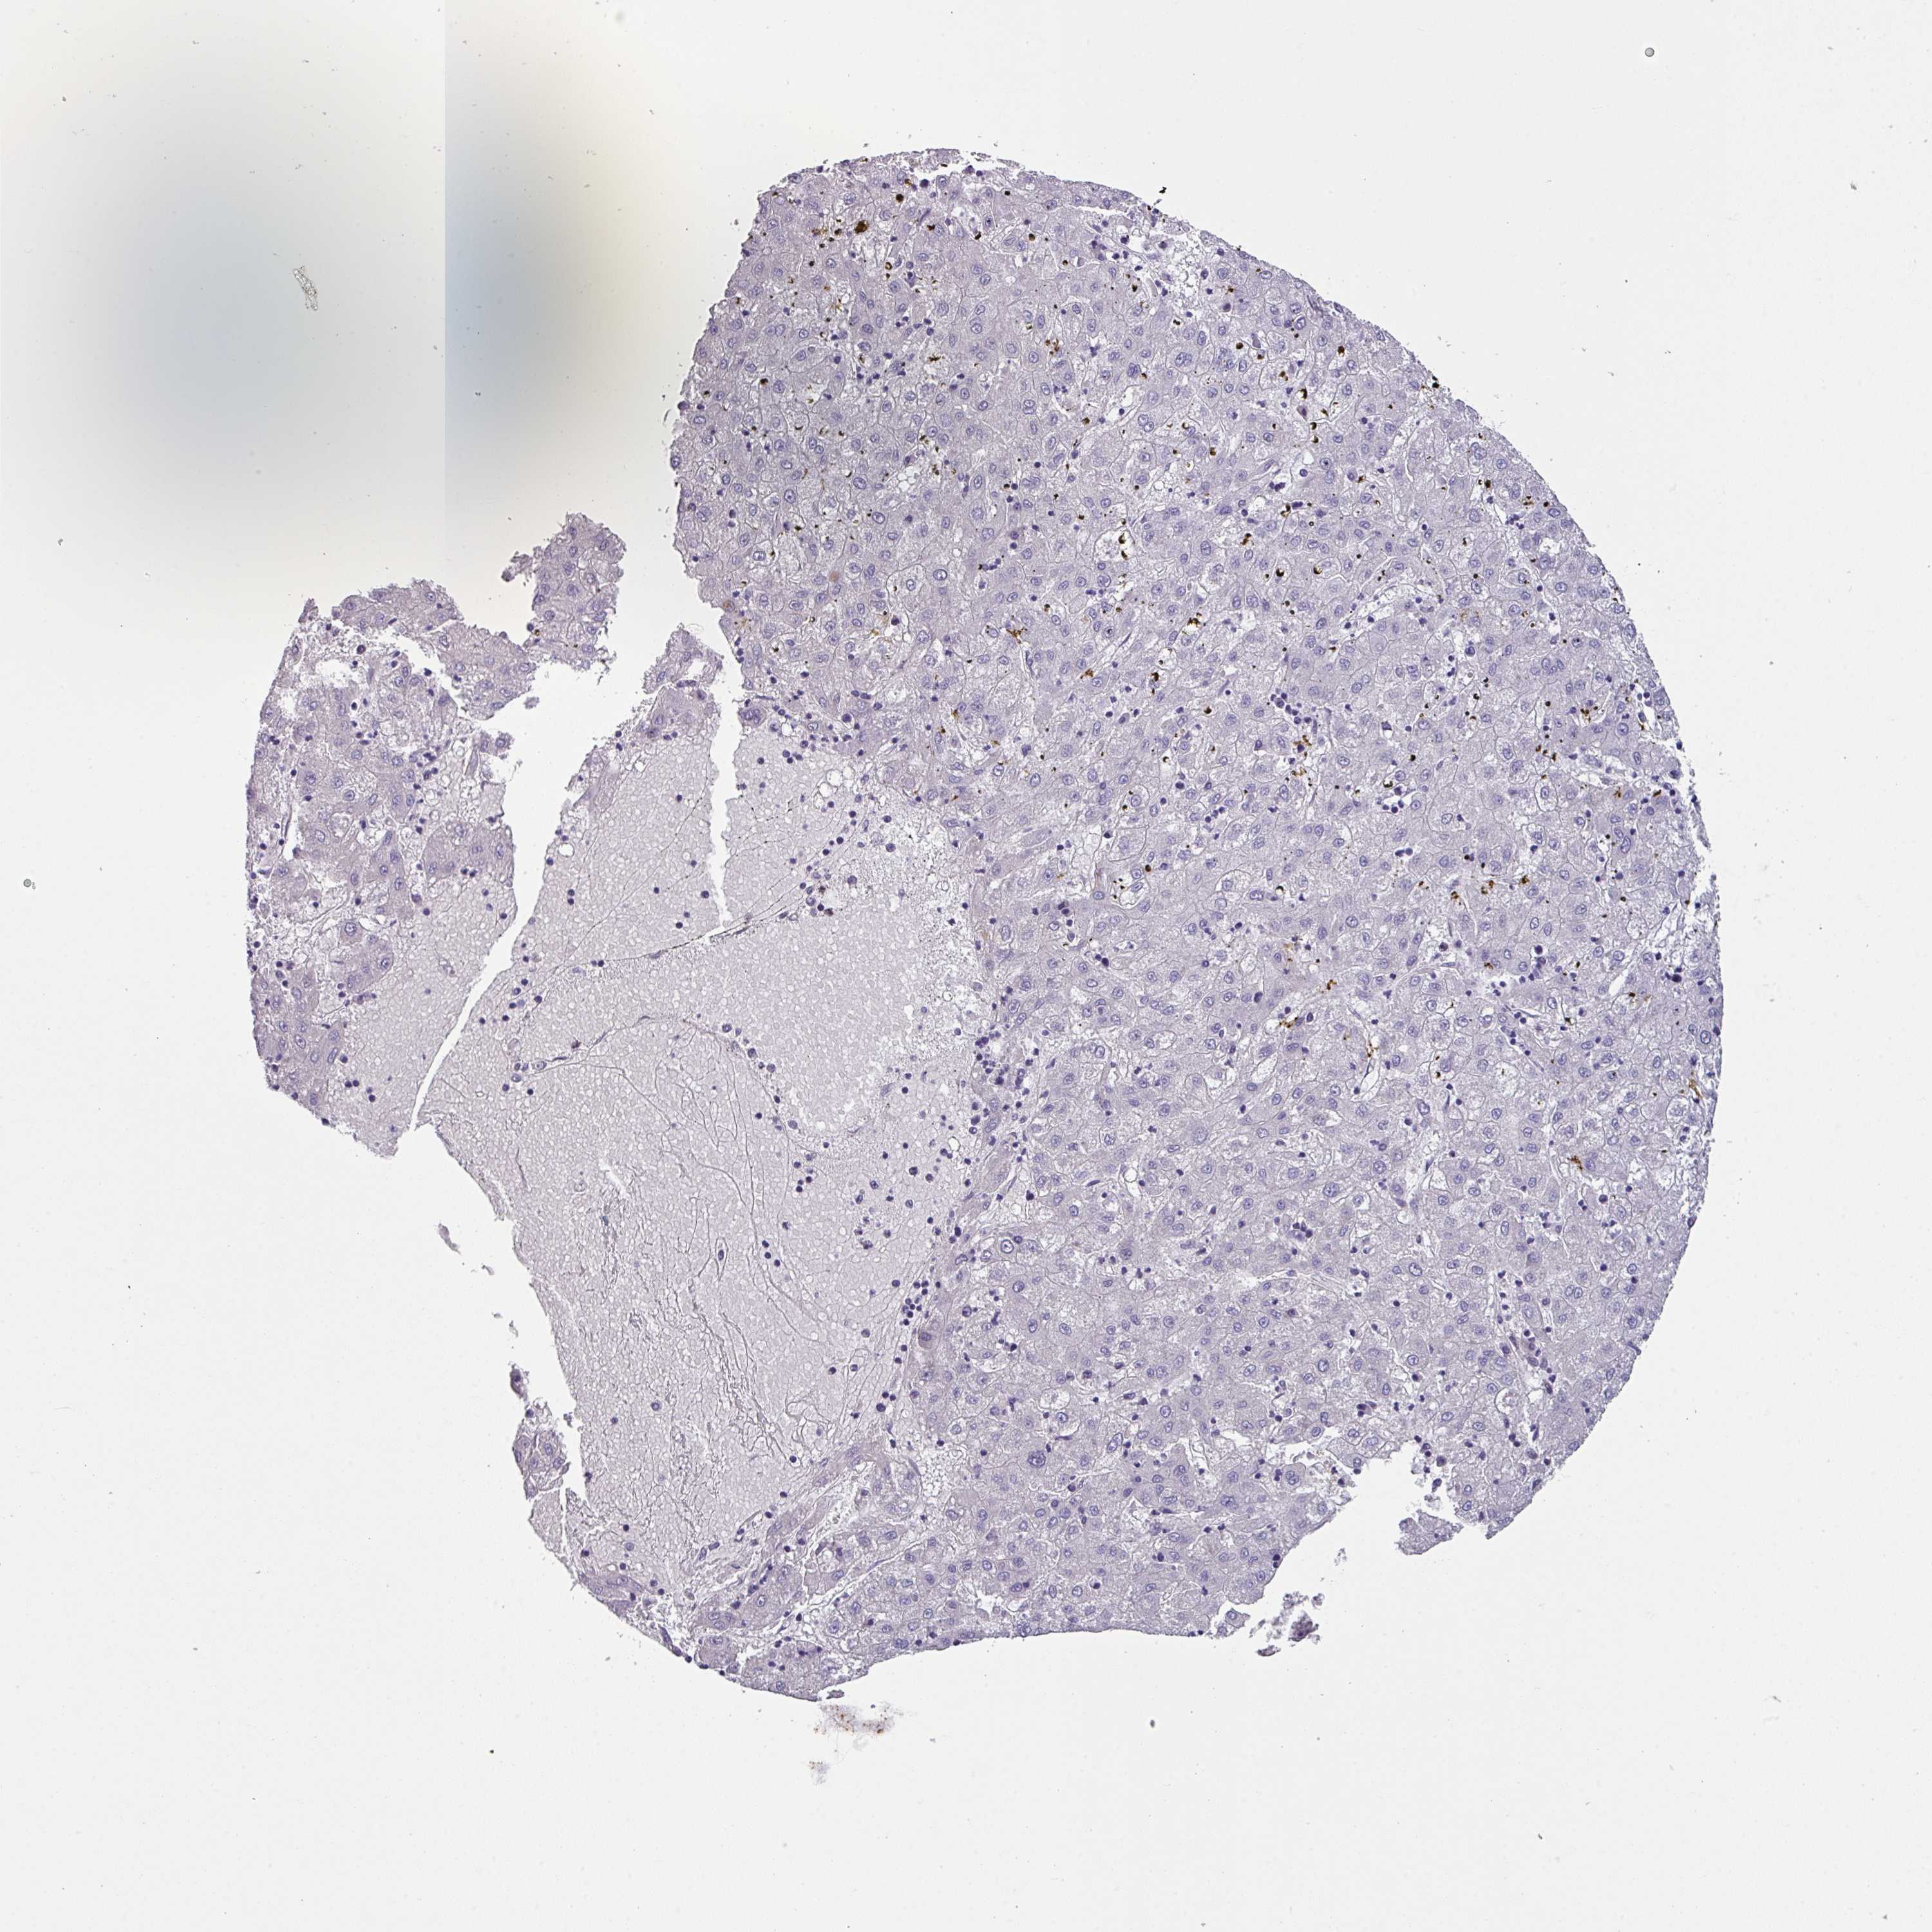

LIVER CANCER - Protein expressioni

A mouse-over function shows sample information and annotation data. Click on an image to view it in a full screen mode. Samples can be filtered based on level of antibody staining by selecting one or several of the following categories: high, medium, low and not detected. The assay and annotation is described here.

Note that samples used for immunohistochemistry by the Human Protein Atlas do not correspond to samples in the TCGA dataset.

Antibody stainingi

Antibody staining in the annotated cell types in the current human tissue is reported as not detected, low, medium, or high, based on conventional immunohistochemistry profiling in selected tissues. This score is based on the combination of the staining intensity and fraction of stained cells.

Each image is clickable and will lead to virtual microscopy that enables deeper exploration of all samples and also displays staining intensity scores, fraction scores and subcellular localization as well as patient and tissue information for each sample.

Antibody HPA053085

Staining

High

Medium

Low

Not detected

Intensity

Strong

Moderate

Weak

Negative

Quantity

>75%

75%-25%

<25%

None

Location

Nuclear

Cytoplasmic/membranous

Cytoplasmic/membranous,nuclear

Cholangiocarcinoma

Carcinoma, Hepatocellular, NOS